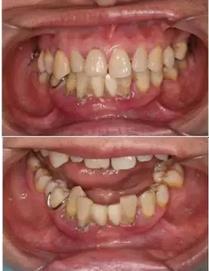

▲ 女性,42歲,牙周病,下前牙固定不良修復(fù)體,基牙炎癥、松動(dòng)。

▲ 拆除不良修復(fù)體,拔除松動(dòng)牙

初診時(shí)下前牙不良修復(fù)體

去除不良修復(fù)體后鄰牙松動(dòng)

拔牙后照片